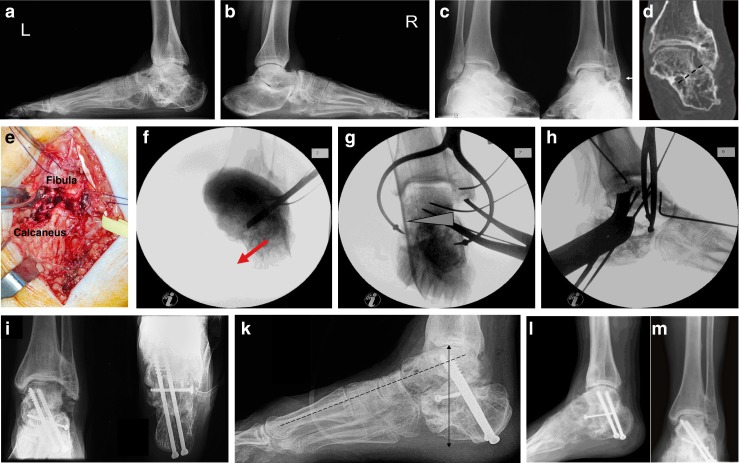

Fig. 1.

a–c Talar malunion (type I) with incongruity of the ankle and subtalar joints secondary to a displaced talar body fracture three months previously. d–e A medial malleolar osteotomy is carried out and a femoral distractor is used to obtain a good overview of the ankle and subtalar joints. f The talar dome can be corrected anatomically at the ankle, the subtalar joint is reduced congruent to the posterior facet of the calcaneus but a defect remains after removal of small fragments. g–i Seven years later the patient is pain free during activities of daily living with only mildly restricted subtalar motion despite radiographic signs of post-traumatic arthritis